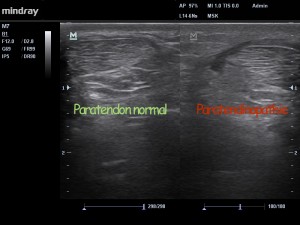

Fig2 . Etude comparative des 2 tendons, mettant en évidence la paratendinopathie.

Chez notre patient, l’échographie (Fig 1 – 3 ) montre la présence d’un mécanisme inflammatoire actif, avec présence d’un exsudat au niveau de para-tendon.  On parle précisément d’inflammation fibrineuse dans notre cas. SI la pathologie s’installe dans le temps, la présence de fibrinogène (grosse protéine présente dans le plasma sanguin) va conduire à la prolifération de fibroblastes (petites cellules notamment impliquées dans la fabrication du collagène et certaines protéines du tissu conjonctif ). Le para-tendon va alors s’épaissir, et des adhérences vont se former entre le para-tendon et le tendon, mettant en péril la vascularisation de ce dernier.